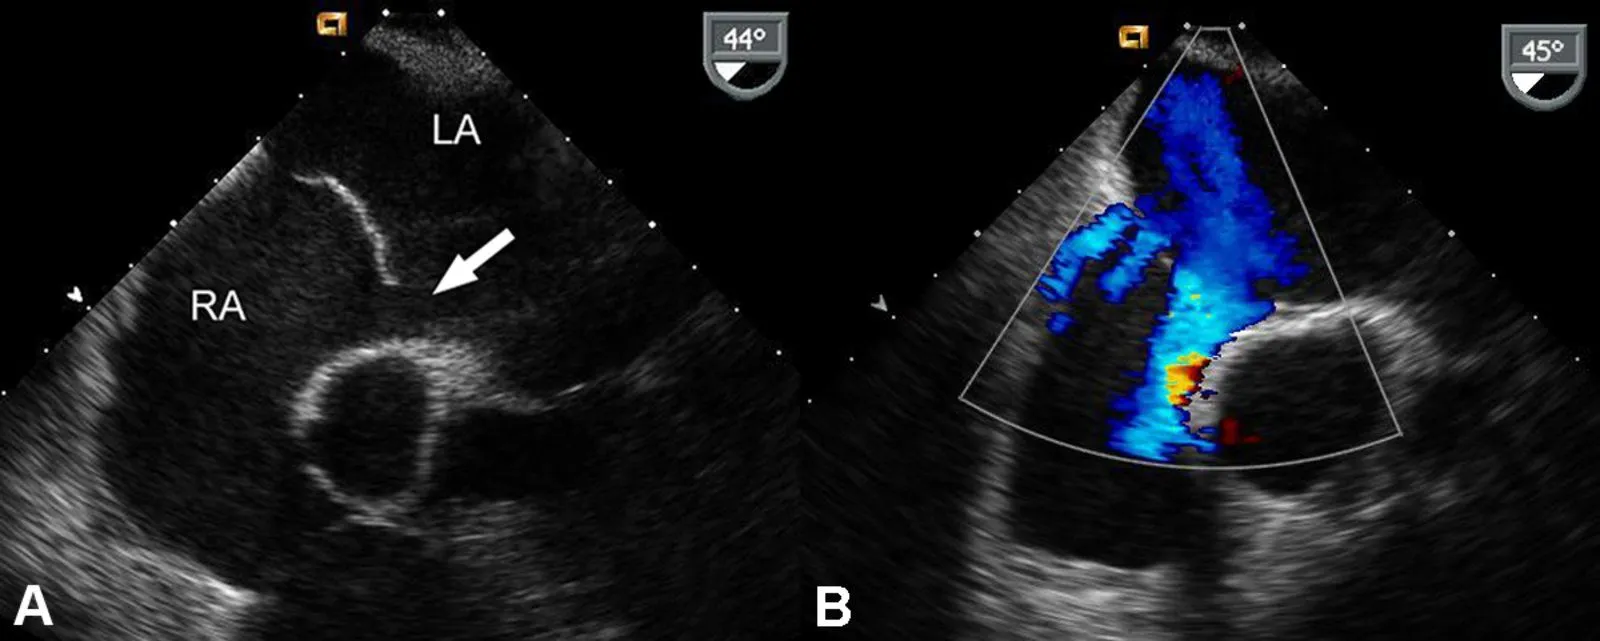

What does this echocardiogram show?

{{c1::Atrial septal defect}}

A defect (white arrow) located between the left atrium (LA) and right atrium (RA) can be seen on the regular ultrasound image (A). There is also an atrial septal aneurysm bulging into the left atrium just below the defect. The color Doppler ultrasound image (B) shows the blood flow through the defect.